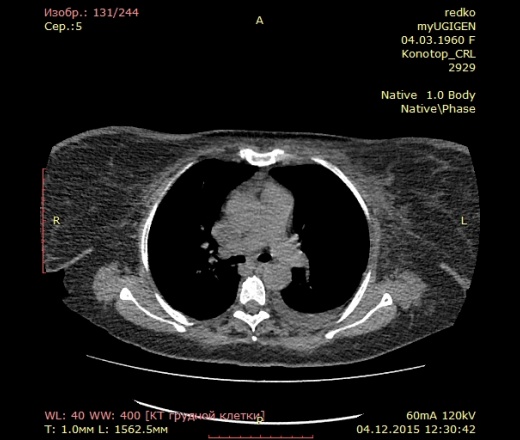

На кт видно кости

На кт видно кости 82 фото